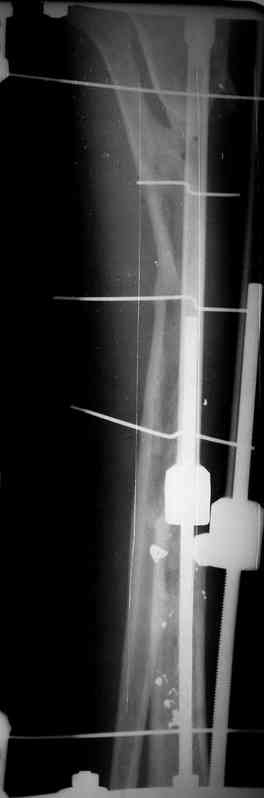

Пациент 19 лет, производственная травма, придавлен тяжелой плитой. Политравма (ISS 21).

1 - рентгенограмма (прошу прощения за качество) при поступлении;

2 - внешний вид голени;

Произведено ПХО, acute shortening (5 см), фиксация стержневым аппаратом Hoffman.

3,4 - через 4 недели наложен спице-стержневой аппарат, произведена остеотомия большеберцовой кости в верхней трети, раны зажили, проводилась дистракция в аппарате.

5, 6 - через 2,5 мес после травмы выполнен закрытый остеосинтез блокируемым штифтом.

7, 8, 9, 10, 11 - через 8 мес после травмы перелом сросся.

Пациент ходит без дополнительной опоры, не хромает (видеоролик выложил сюда

http://rapidshare.com/files/14134274/Patient_B.AVI.html, вес 892 кб).